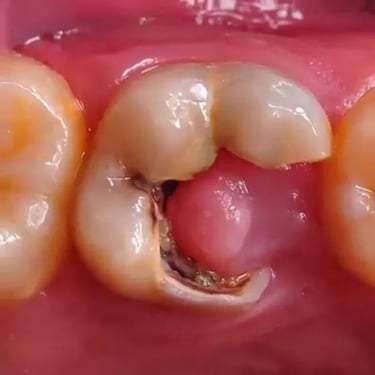

Pulpitis Crónica Hiperplásica

La pulpitis crónica hiperplásica es una inflamación de la pulpa con crecimiento excesivo de tejido pulpar a través de una caries abierta.

Los pacientes notan un tejido rojo que sobresale de la cavidad dental.

El tratamiento incluye la eliminación del tejido afectado y un tratamiento de conducto. Es crucial tratar la caries para evitar infecciones adicionales.